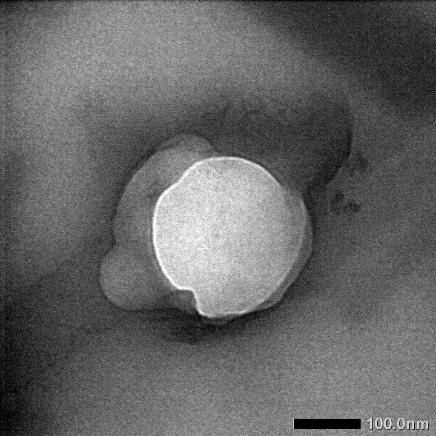

TEM test

The myricetin nanophytosome sample used for the TEM test is the myricetin formula 6 nanophytosome sample with the Myricetin: Phosphatidylcholine: Cholesterol (1: 1: 0.4) test used to see the morphology. The use of 1-mole phosphatidylcholine in the formula can prevent agglomeration so that the particles do not grow bigger. Observations with TEM nanophytosome formula 6 show irregularly shaped round nanoparticles vesicles. The micrograph of the TEM results can be seen in fig. 2. The polar portion of the vesicles is shown in black, while the transparent or colorless portion indicates the presence of a non-polar compound. The method of manufacture influences the shape of vesicles, in some previous studies, the shape of particles produced was spherical and uniform, but in this study, the shape of the resulting vesicles was irregularly rounded. This needs to be developed in further research to find other manufacturing methods to produce better vesicle shapes.

Fig. 2: TEM formula 6 test results